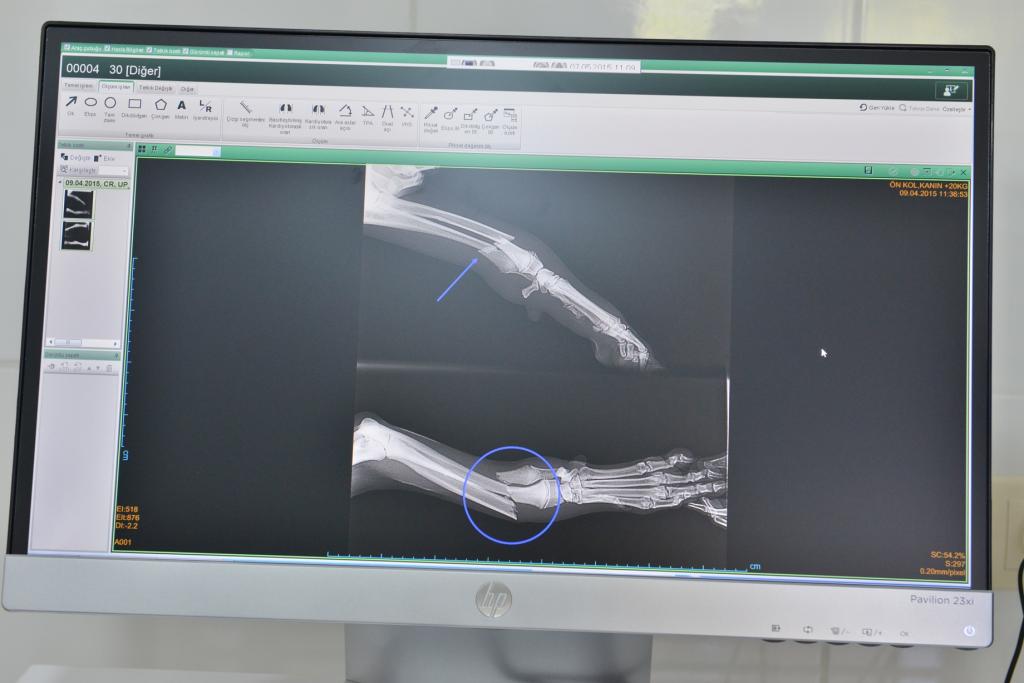

Hizmetleriyle bir çok Avrupa ülkesinden de tam not alan Konyaaltı Belediyesi Sokak Hayvanları Rehabilitasyon Merkezi, inşası tamamlanan laboratuar ile de hizmet çıtasını yükseltiyor. Tam donanımlı laboratuar da kırık, çıkık, trafik kazası yaralanmaları tedavi edilebiliyor; biyokimyasal testler yapılabiliyor.